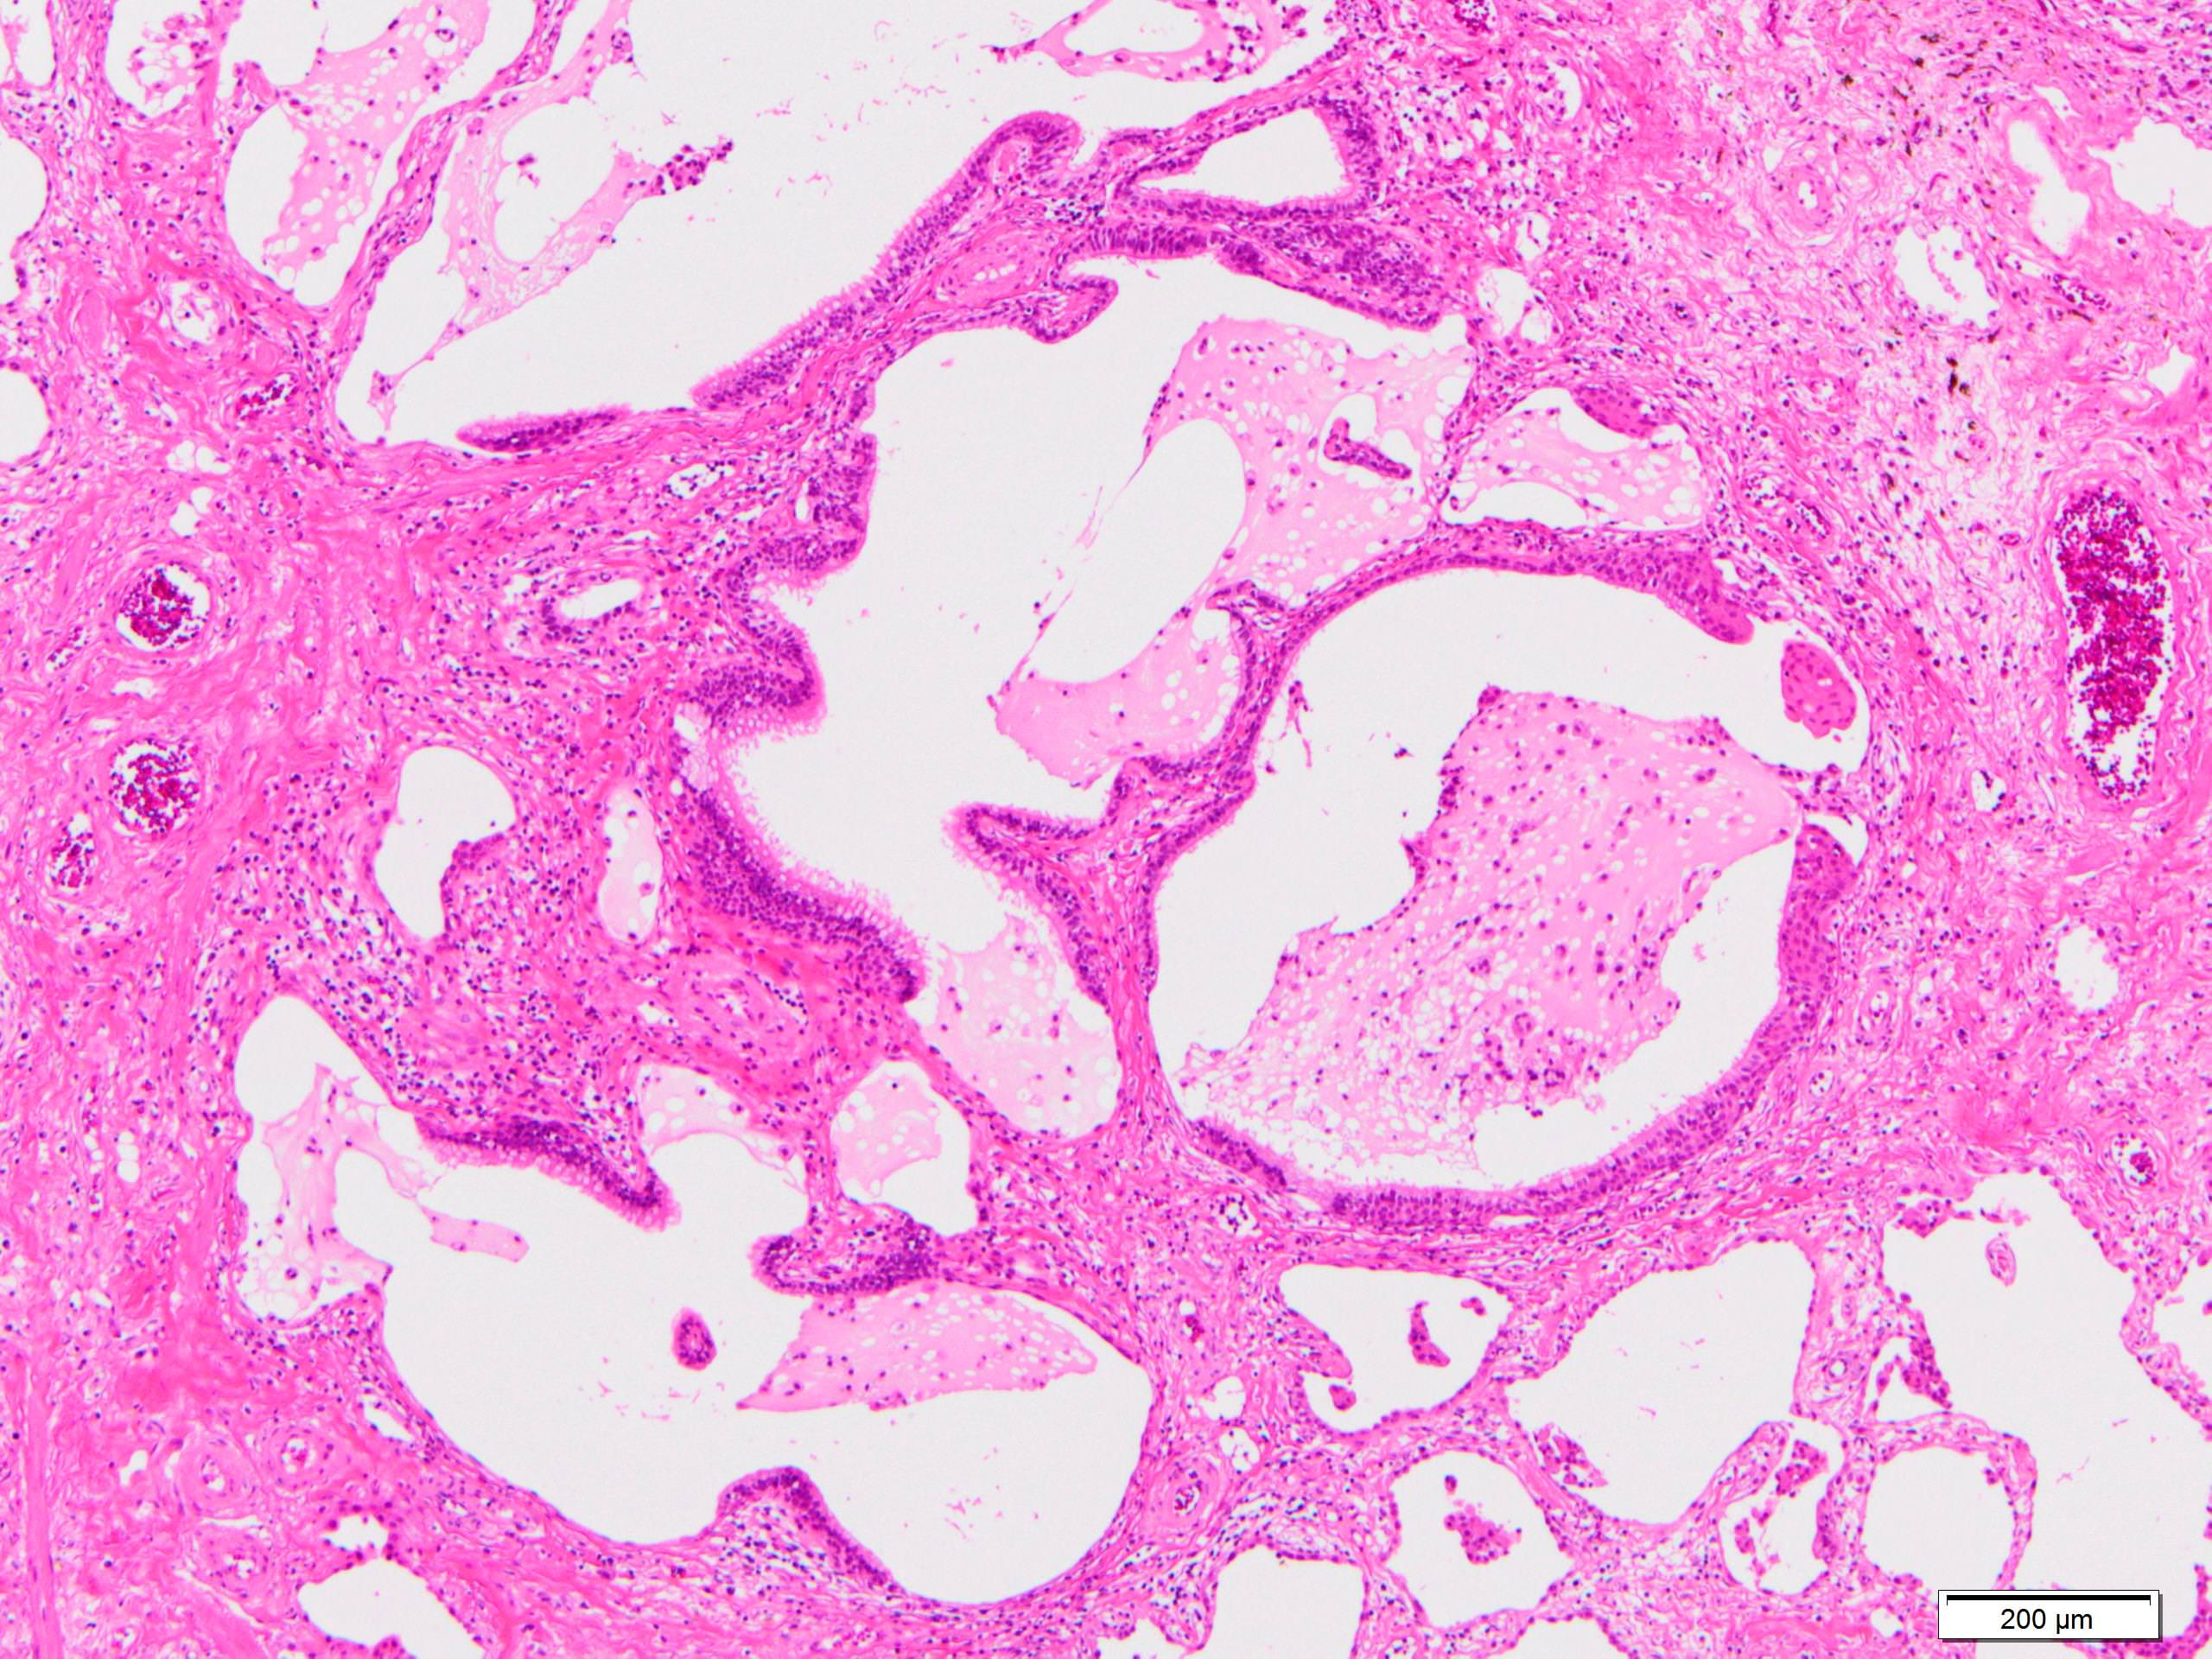

Microscopic (histologic) description

- Since there are few specific findings for NSIP pattern, it is essential to exclude other lung diseases on histology (Am J Respir Crit Care Med 2008;177:1338)

- Characteristic findings of NSIP pattern

- Diffuse and uniform inflammation ("temporal homogeneity") on low power of alveolar wall, bronchovascular bundles and pleura

- There are usually no normal alveolar walls in the affected lobules

- Cellular or fibrotic change

- Lymphocytic or plasmacytic infiltration

- Loose fibrosis

- Lung architecture is frequently preserved

- "Cellular NSIP" or "fibrotic NSIP" can be stated specifically in pathologist report

- Diffuse and uniform inflammation ("temporal homogeneity") on low power of alveolar wall, bronchovascular bundles and pleura

- Features of interstitial pneumonia with autoimmune features (IPAF) (Chest 2010;138:251):

- Lymphoid aggregates with germinal center

- Extensive pleuritis

- Prominent plasmacytic infiltration

- Dense perivascular collagen

Microscopic (histologic) images

Scroll to see all images.

Contributed by Akira Yoshikawa, M.D.

Images hosted on other servers:

Contributed by Akira Yoshikawa, M.D.

Images hosted on other servers: